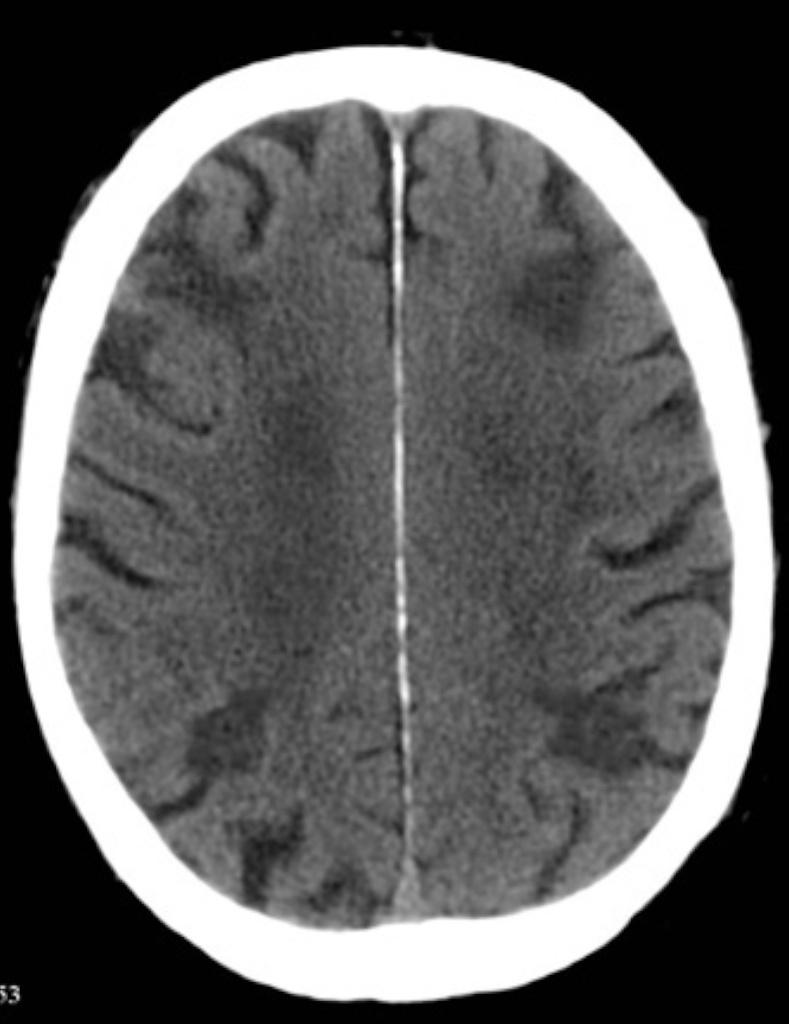

Normal